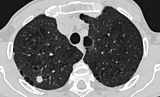

Чтобы уточнить диагноз, пациенту провели необходимые исследования, включая компьютерную томографию лёгких, бронхоскопию и современный тест на туберкулёз — ТиграТест. По итогам обследования медики приняли решение о хирургическом удалении небольшого участка лёгкого.